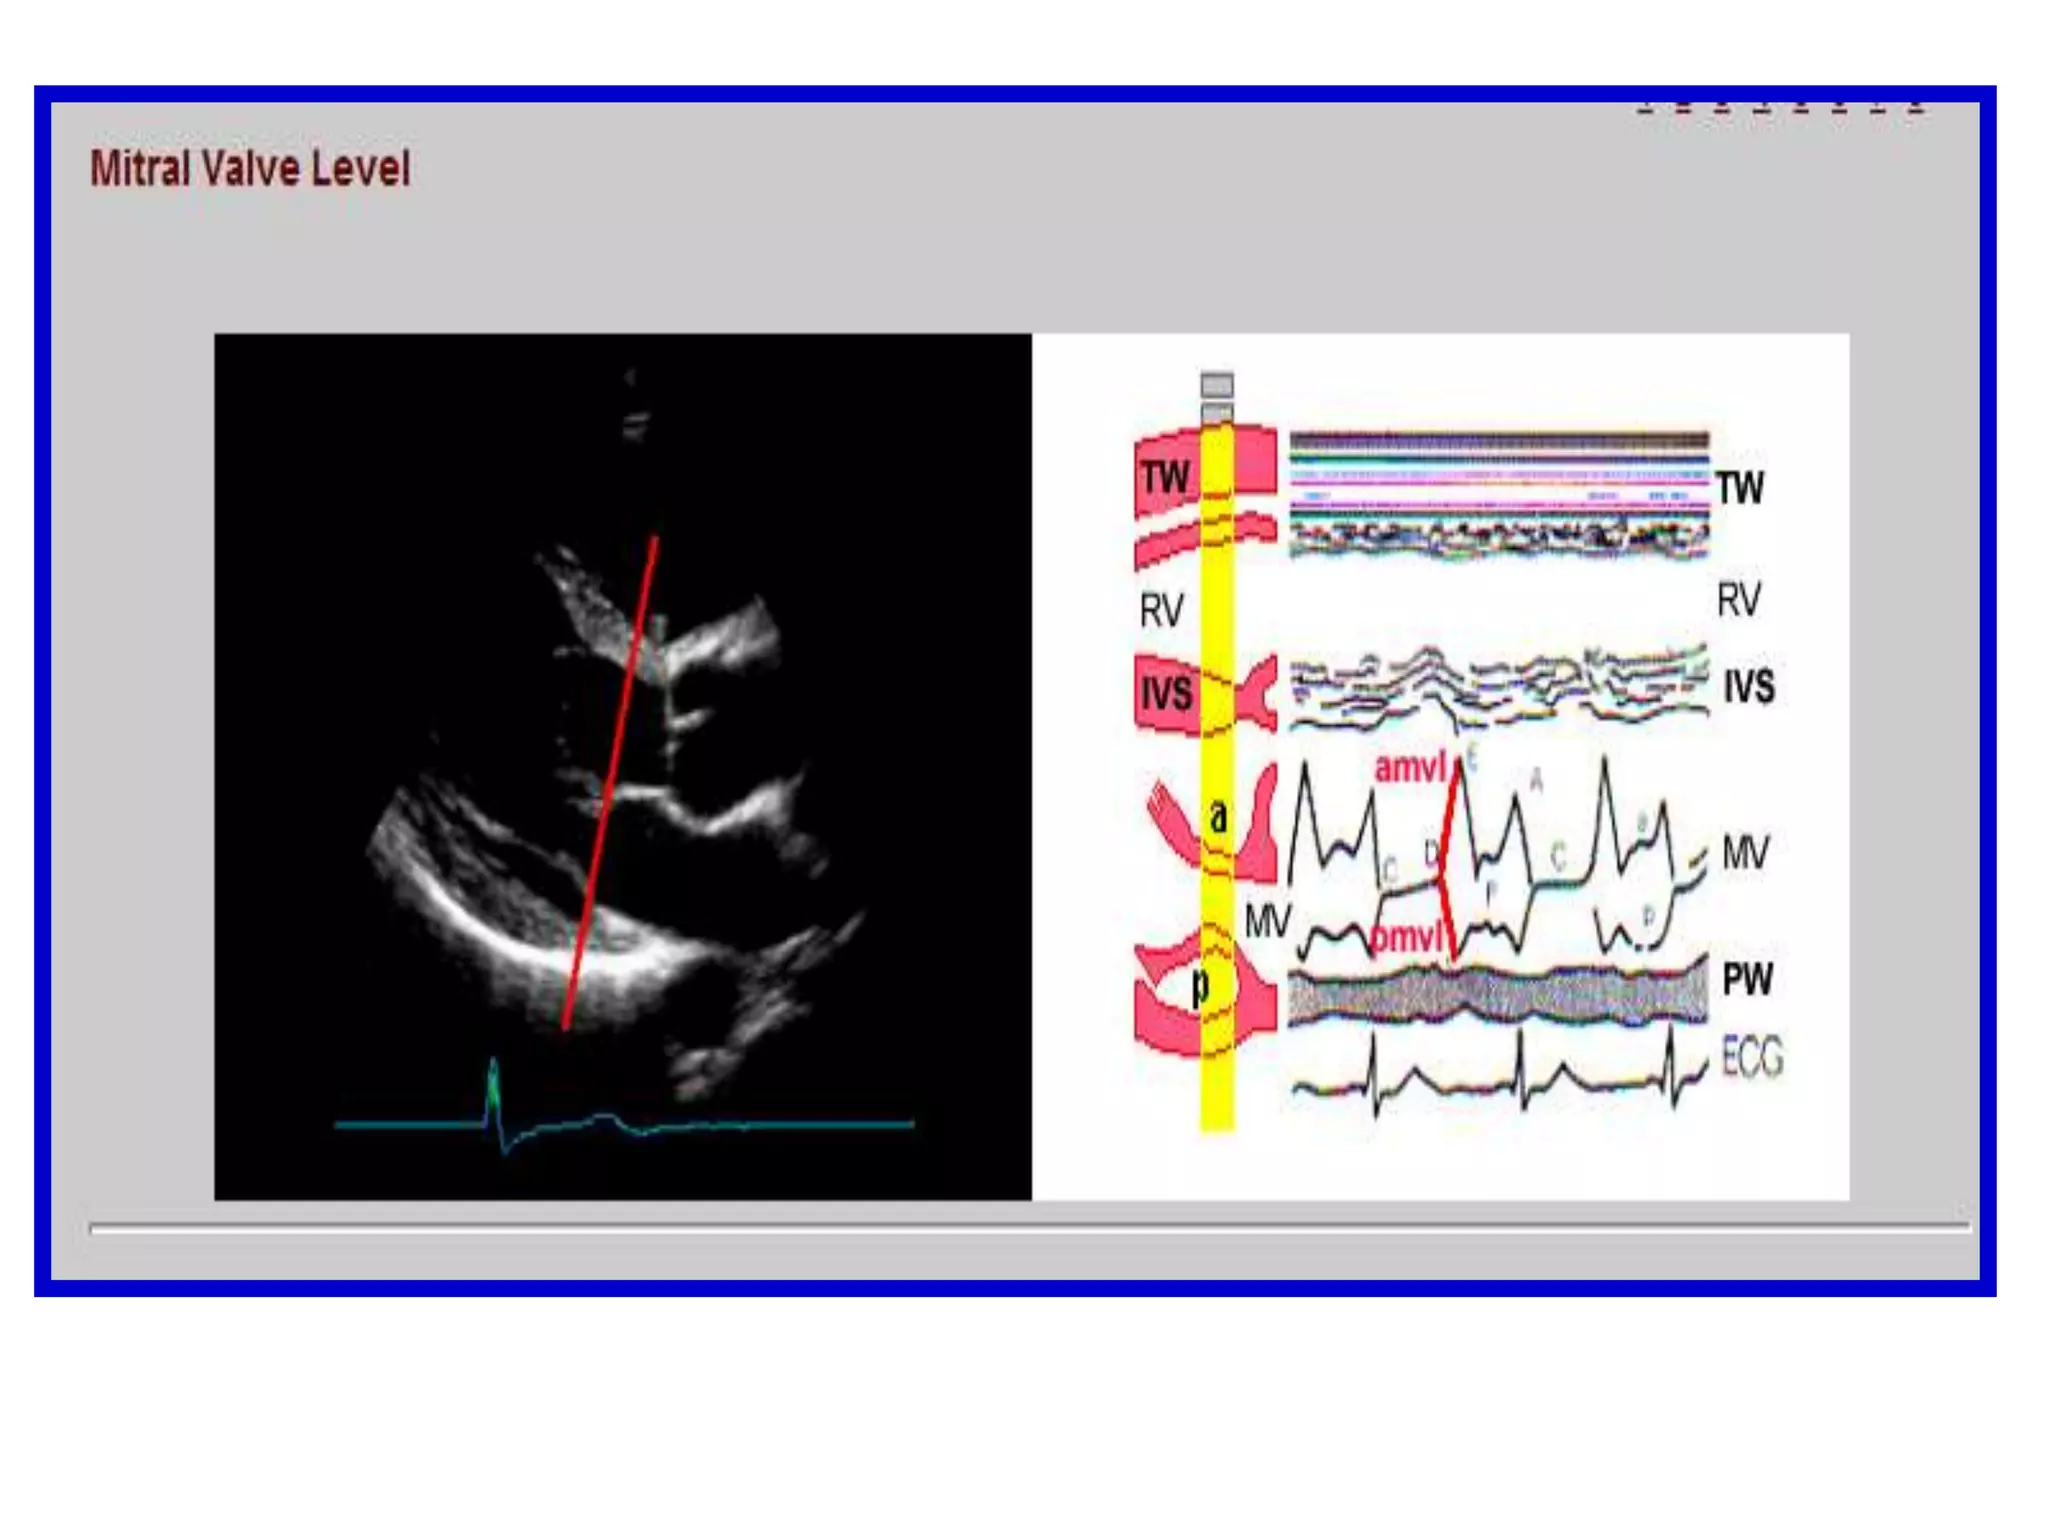

Parasternal Short-Axis ViewMitral Valve LevelThe anterior and posterior mitral leaflets are seen as they open in diastole and close in systole

Parasternal Short-Axis ViewMitral Valve Level

B.  M-MODE ECHOCARDIOGRAPHYa single line of sight is included, the repetition frequency of the pulse transmission is very high and sampling rates of around 1800 cycles/sec are usedContinuously-moving structures may be identified more accurately when motion versus time, as well as depth, is displayed clearly on the M-mode recording

In early diastole, the leaflets separate widely, with the maximum early diastolic motion of the anterior leaflet termed the E point. The leaflets move together in mid-diastole and then separate again with atrial systole, the A point. Closure at the end of diastole is termed C point.